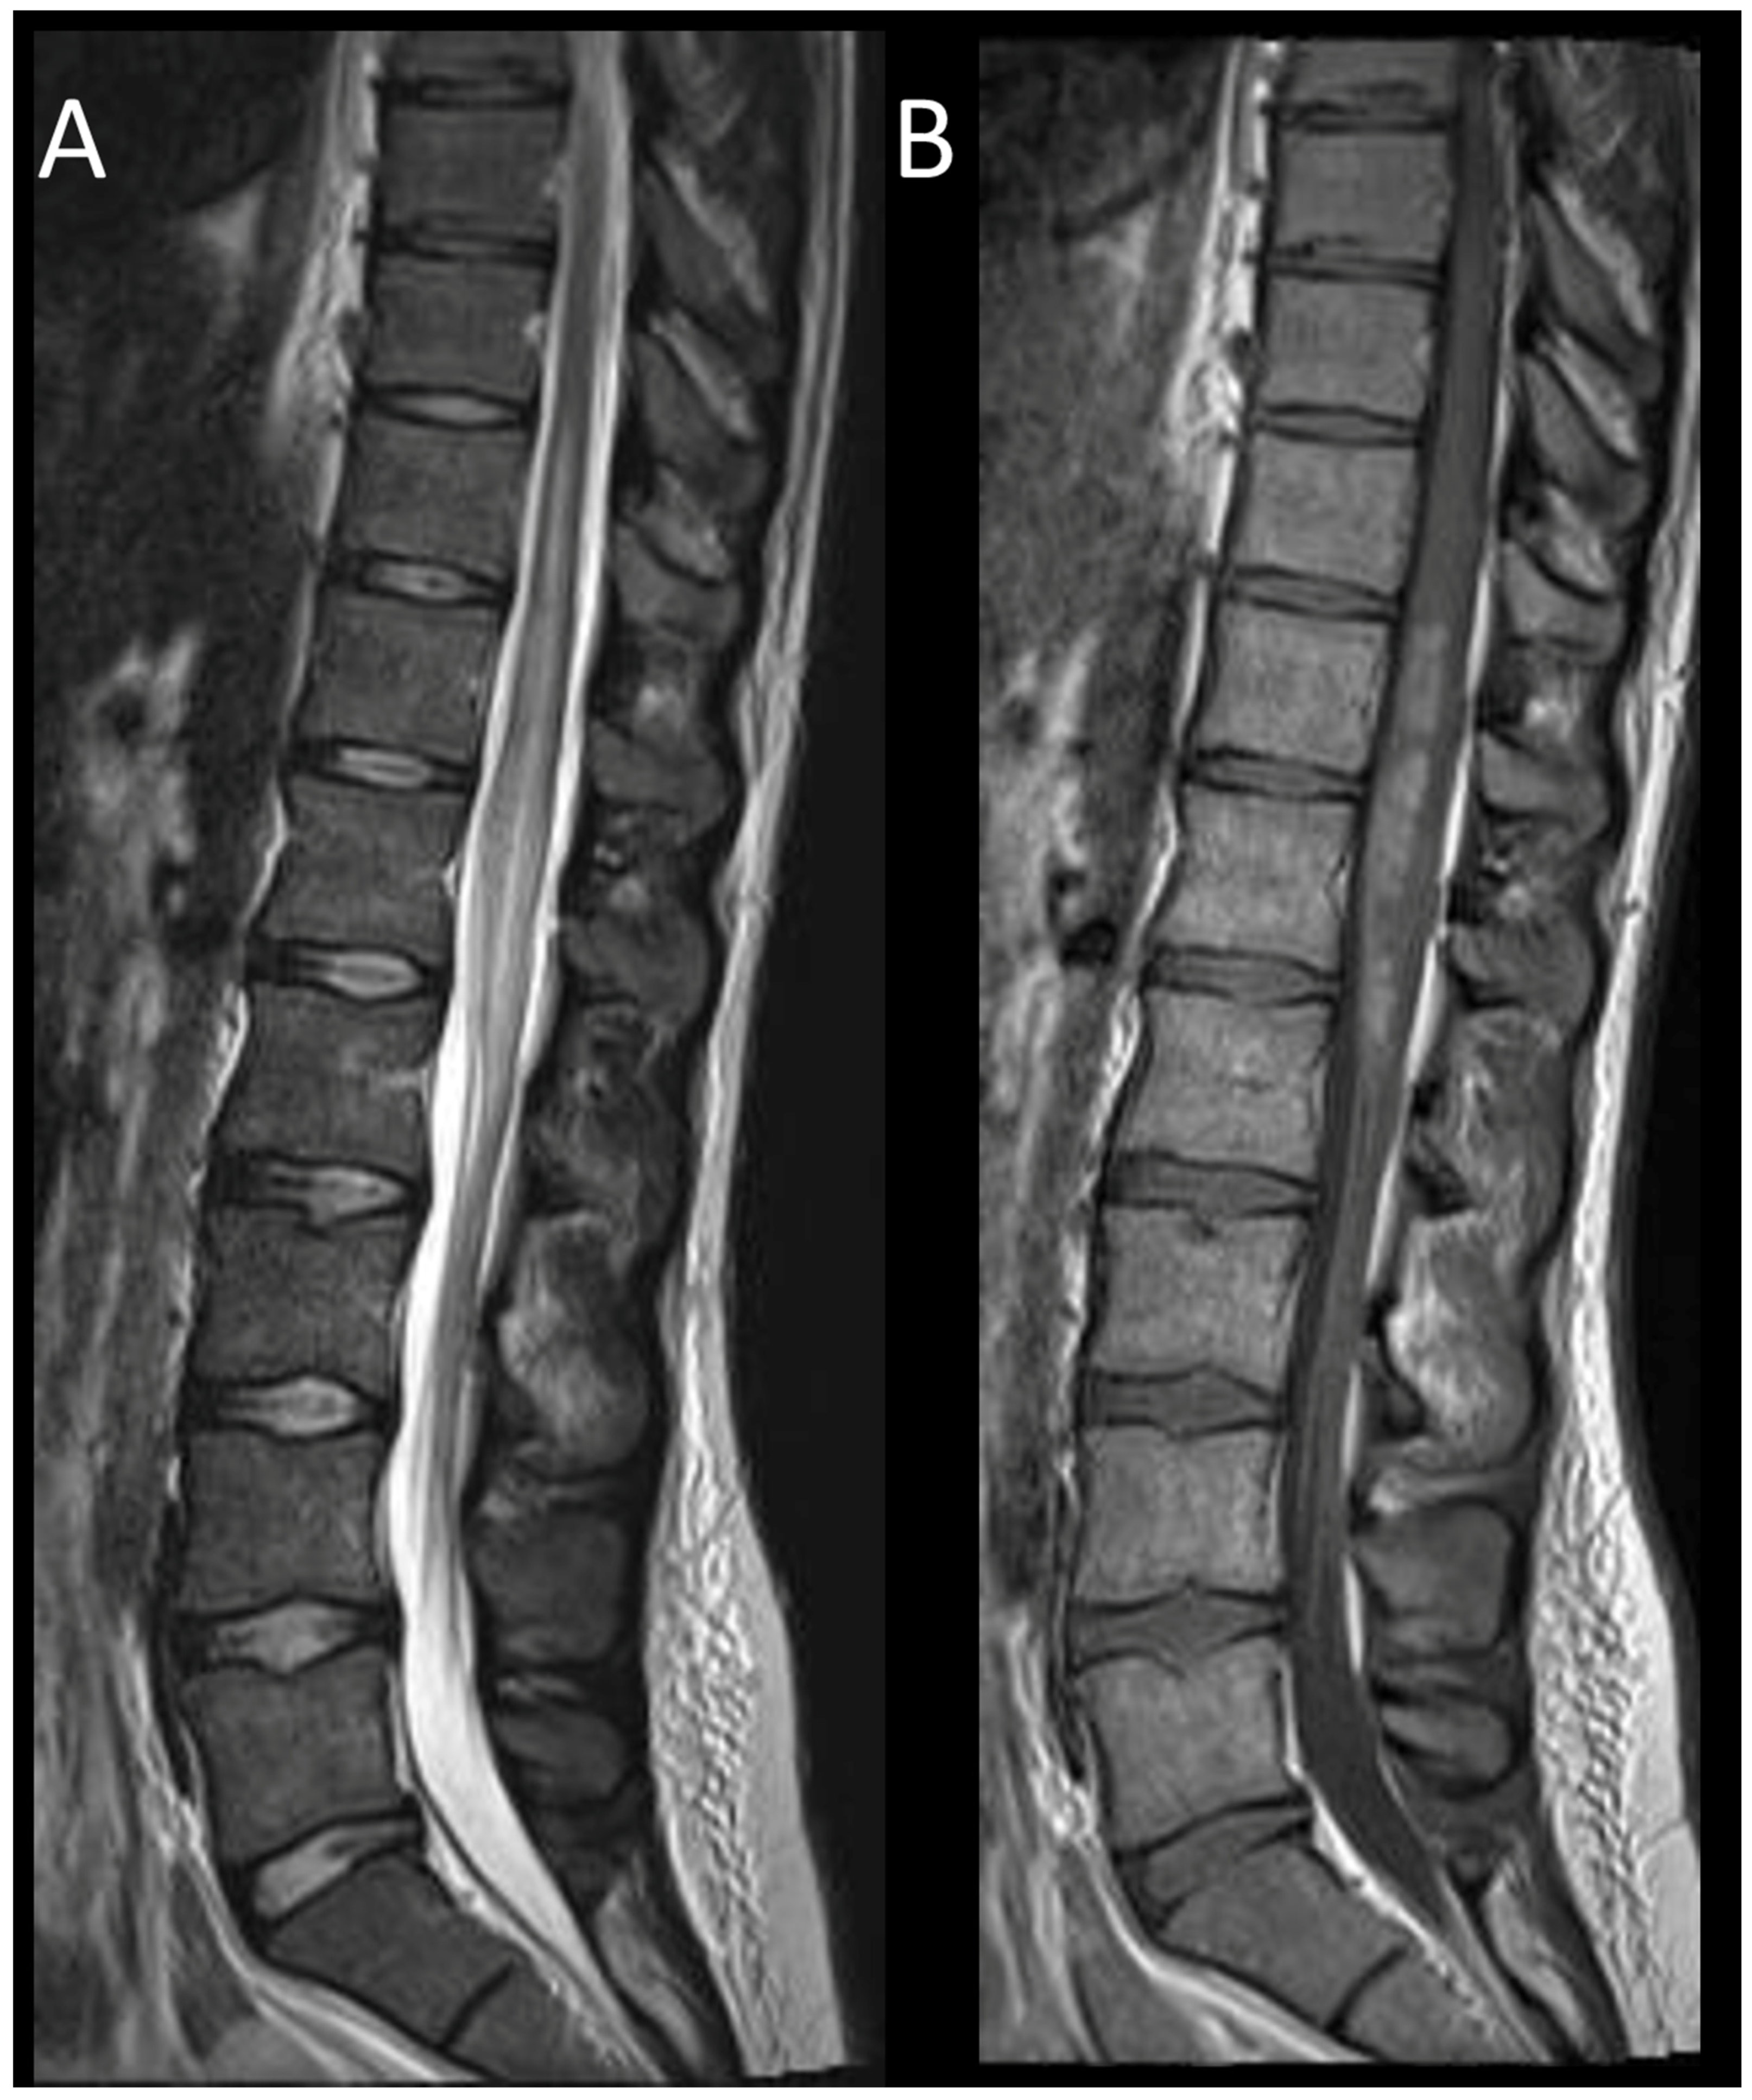

3.3.2. Spinal Dural Arteriovenous Fistula

3.3.3. Spinal Cavernous Malformation